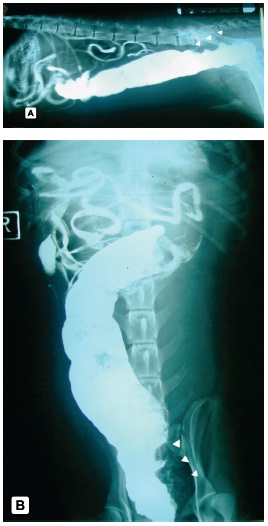

En el estudio de tránsito intestinal se observaron asas intestinales muy distendidas con abundante gas intraluminal y colon aumentado de tamaño en todo su trayecto (megacolon); a la administración del medio de contraste (sulfato de bario), se observó transito normal hasta el colon descendente donde se represó el medio, y en el segmento distal (ampolla rectal) se observó un defecto de llenado muy irregular de aspecto intraluminal (figura 1A y 1B)

FIGURA 1. Estudio radiográfico con medio de contraste.

(A) Vista lateral, se observa el megacolon, las puntas de flecha muestran el defecto de llenado a nivel de la ampolla rectal;

(B) vista ventro - dorsal, se muestra el mismo defecto de llenado.